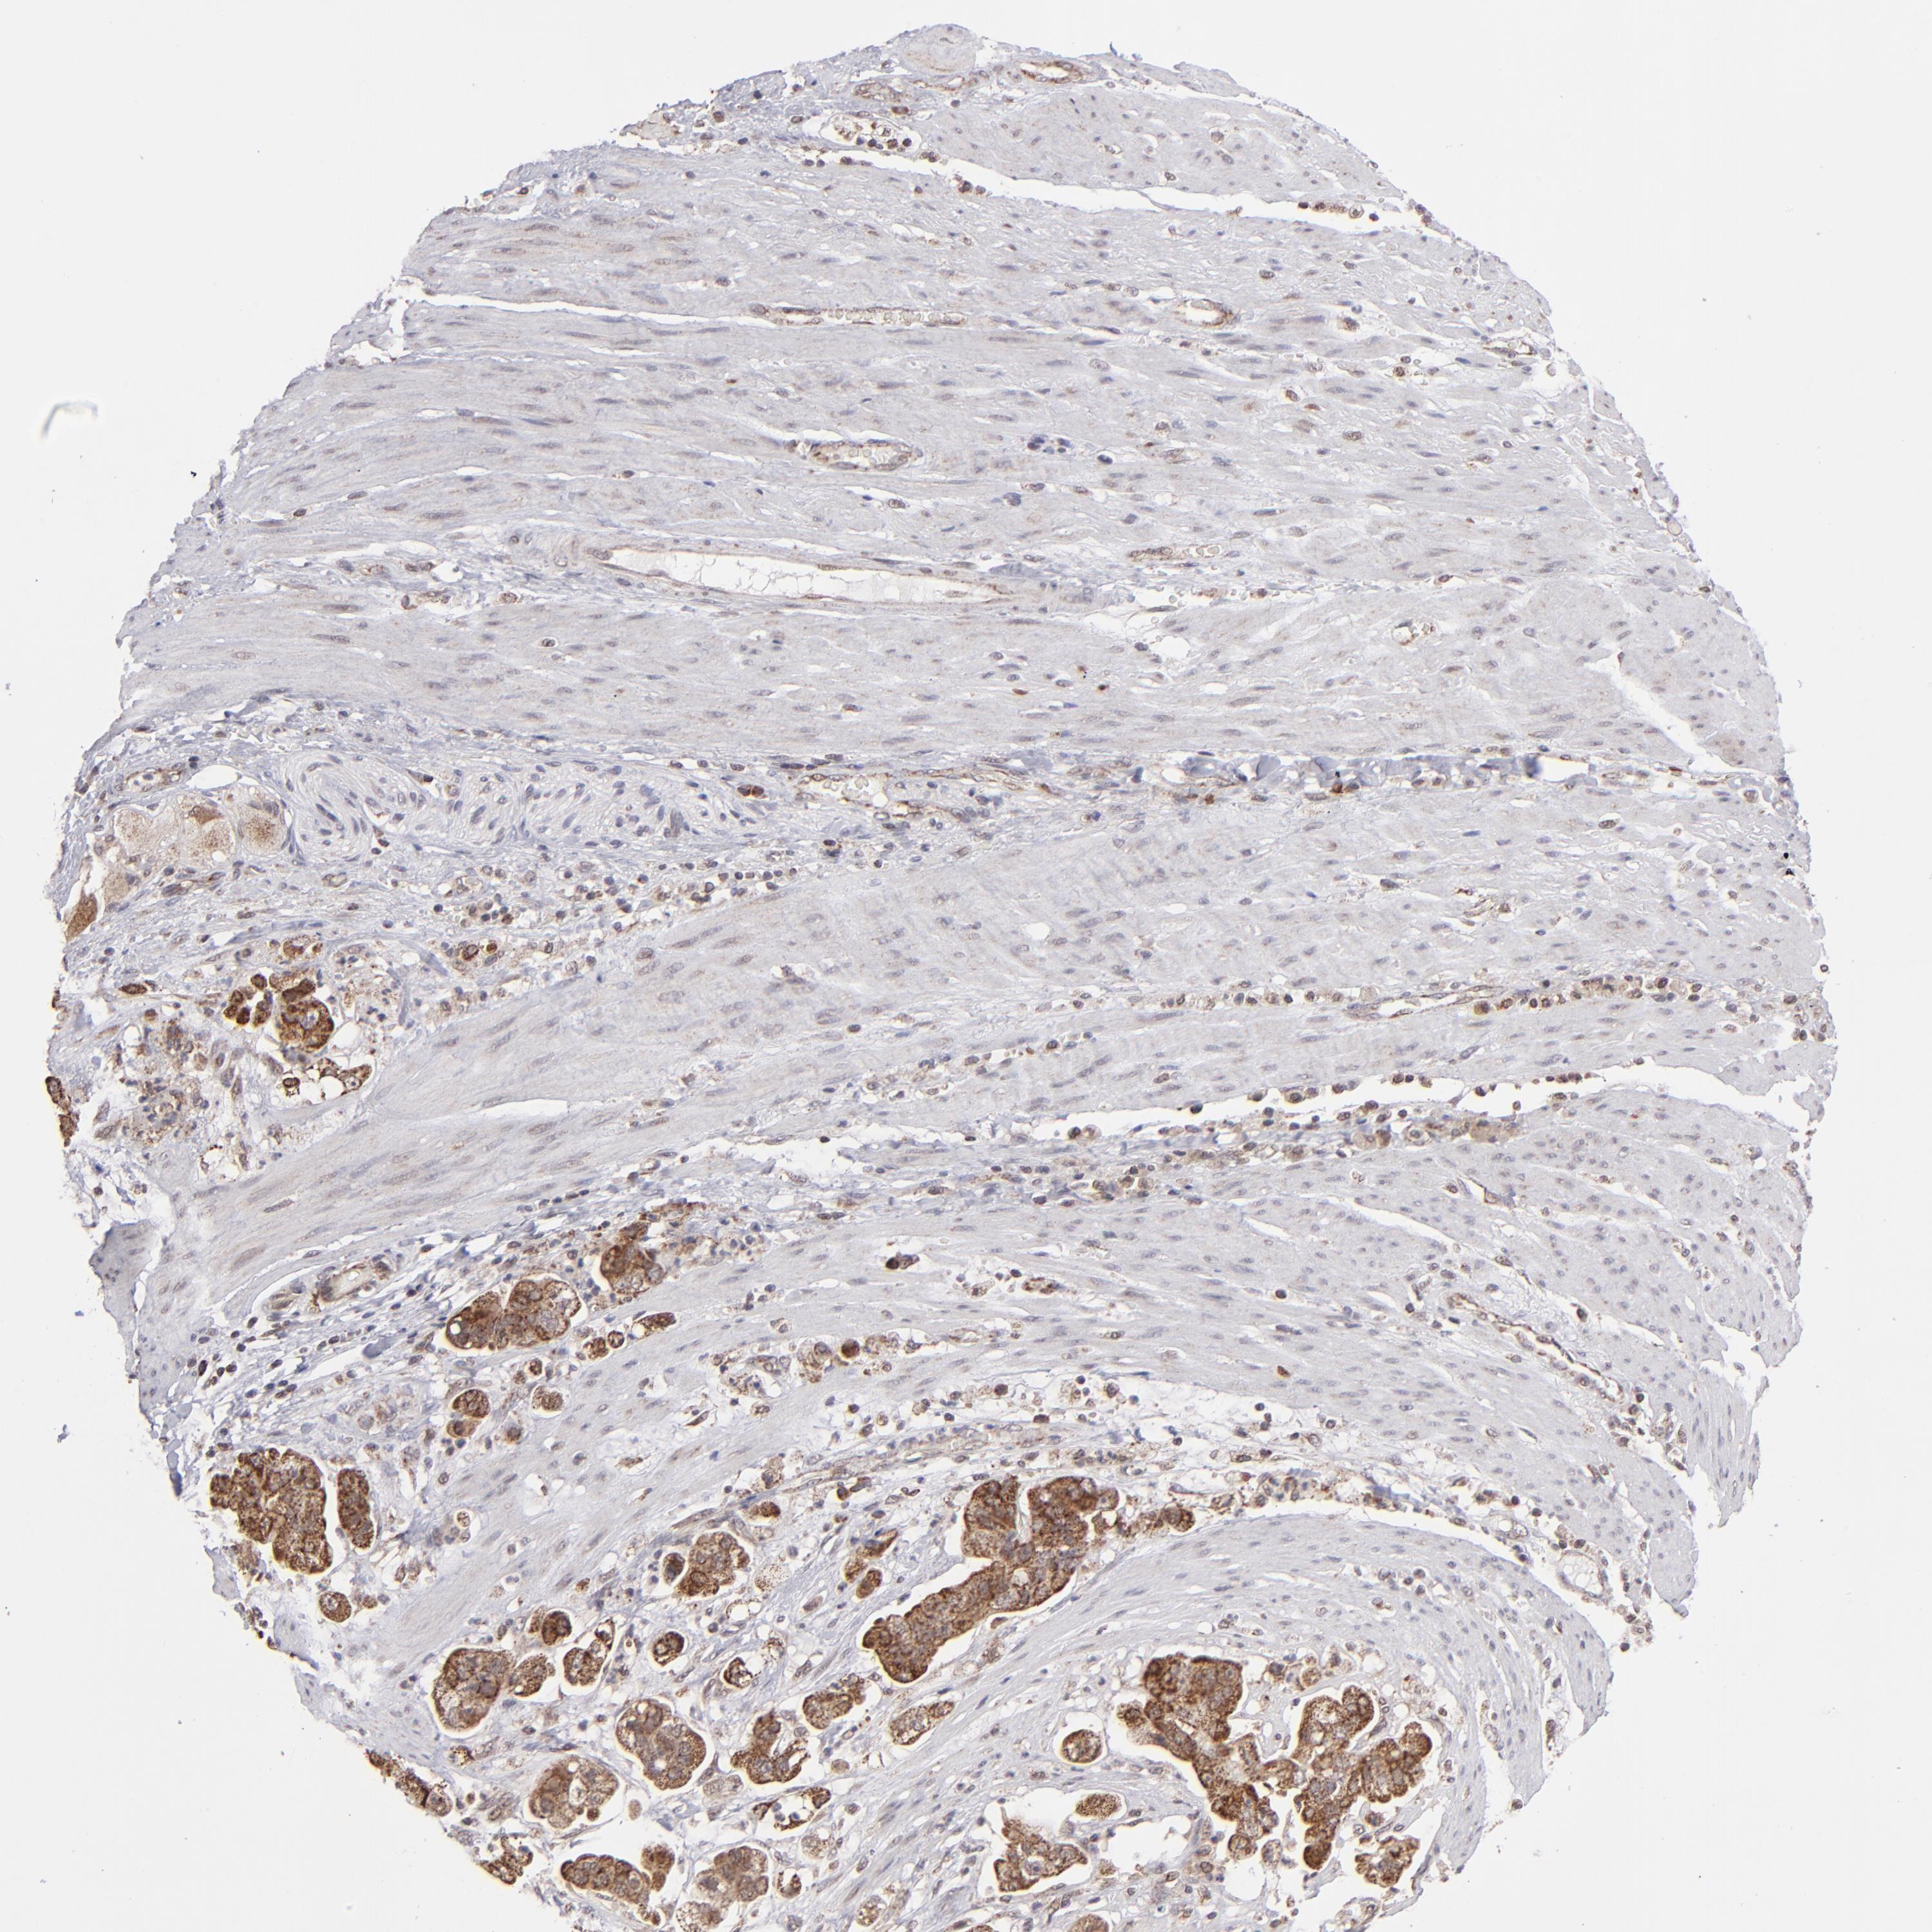

STOMACH CANCER - Protein expressioni

A mouse-over function shows sample information and annotation data. Click on an image to view it in a full screen mode. Samples can be filtered based on level of antibody staining by selecting one or several of the following categories: high, medium, low and not detected. The assay and annotation is described here.

Note that samples used for immunohistochemistry by the Human Protein Atlas do not correspond to samples in the TCGA dataset.

Antibody stainingi

Antibody staining in the annotated cell types in the current human tissue is reported as not detected, low, medium, or high, based on conventional immunohistochemistry profiling in selected tissues. This score is based on the combination of the staining intensity and fraction of stained cells.

Each image is clickable and will lead to virtual microscopy that enables deeper exploration of all samples and also displays staining intensity scores, fraction scores and subcellular localization as well as patient and tissue information for each sample.

Antibody HPA002827

Staining

High

Medium

Low

Not detected

Intensity

Strong

Moderate

Weak

Negative

Quantity

>75%

75%-25%

<25%

None

Location

Nuclear

Cytoplasmic/membranous

Cytoplasmic/membranous,nuclear

Adenocarcinoma, NOS

Adenocarcinoma, High grade